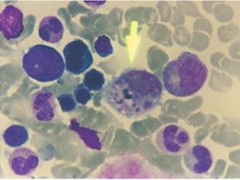

血小板減少、血沉加快、凝血異常是各種出血熱的共同特點。流行性出血熱可見白細胞增多,甚至類似白血病反應;其它出血熱多為白細胞減少。有腎功能衰竭者常有尿素氮增高和電解質紊亂。尿常規檢查,各種出血熱均有程度不等的蛋白、紅細胞、白細胞或管臨床診斷可根據流行病學資料、臨床表現和實驗室檢查結果進行綜合分析。而確診必須有血清學或病毒學的證據。